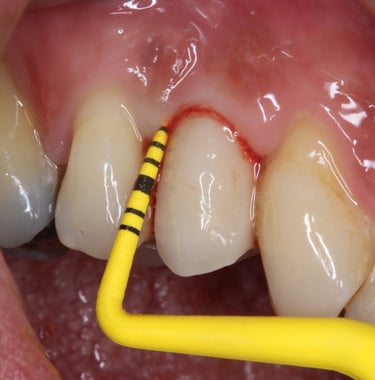

Chirurgie muco-gingivale

Traitement des récessions gingivales